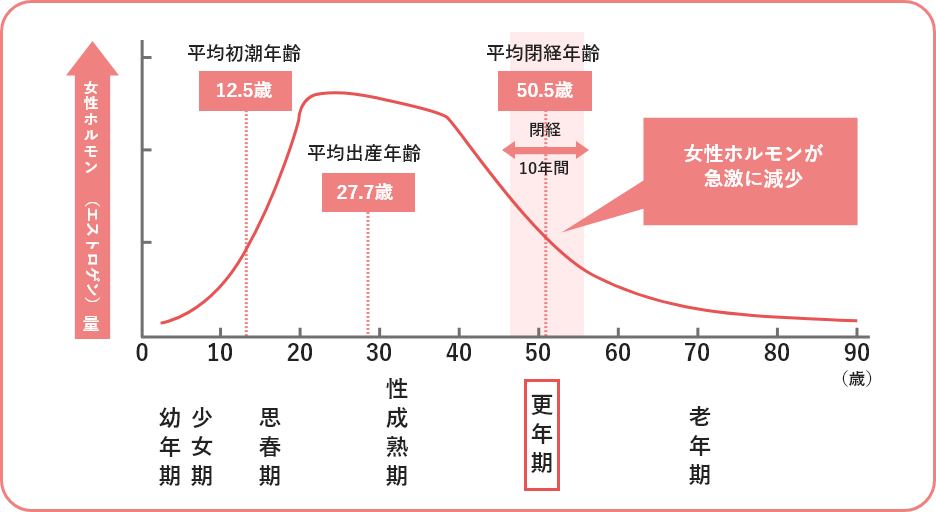

子宮や膣といった女性器は女性ホルモン(エストロゲン)の作用を大きく受ける器官です。一般的に20~22歳ごろそのピークを迎え、その後徐々にホルモンの分泌量は減少してきます。

特に更年期を迎えるとエストロゲンの分泌量は激減し、膣のうるおいが失われ、膣内環境が大きく変化してきます。